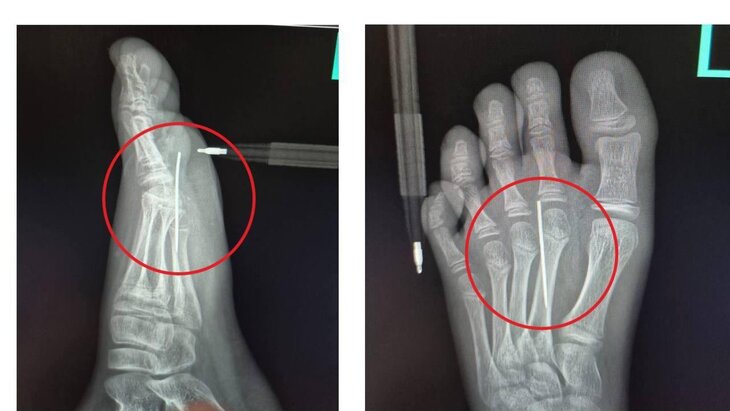

Фото: министерство здравоохранения Московской области

Врачи медучреждения выполнили рентгенографию, по итогам которой подтвердили наличие инородного тела в стопе. Иголка была успешно извлечена при помощи инструмента "Москит". Продолжительность процедуры составила не больше трех минут.